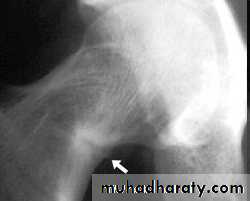

Looser zone

pseudofractures, or Looser's zones in the ribs and pelvis and long bones and vertebra